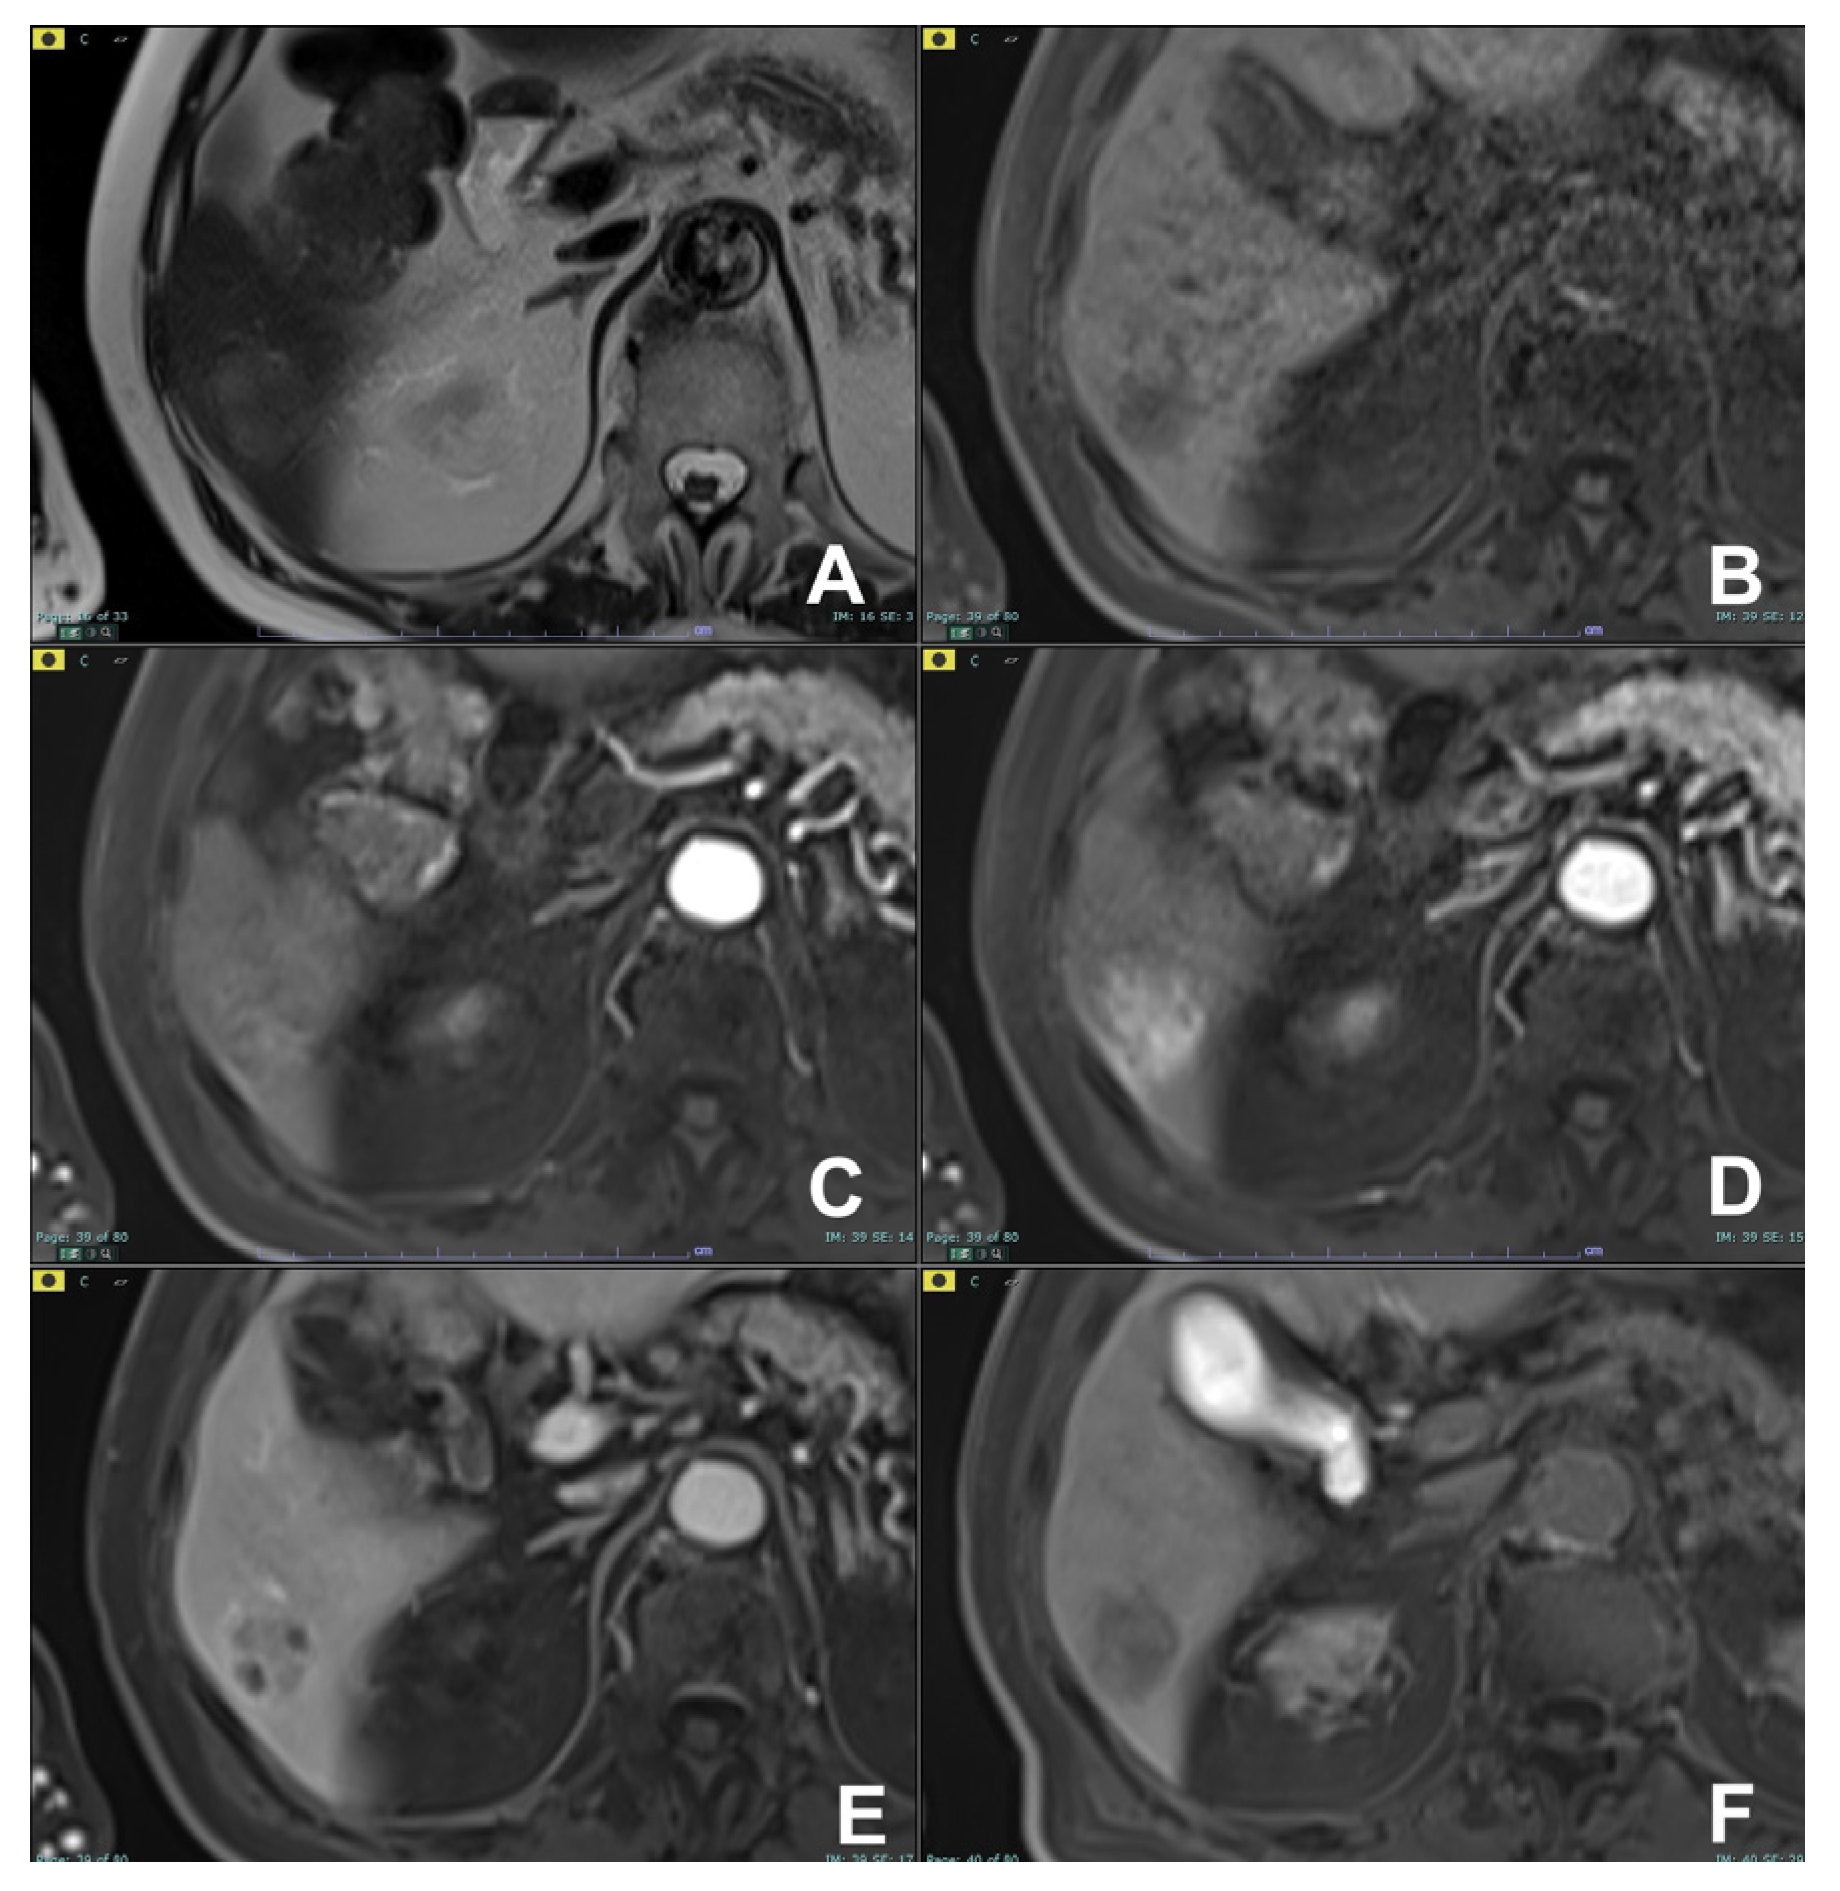

| Acute pancreatitis (AP) | HASTE T2 | AXIAL | -- | Anatomy and analysis of the content of collections |

| Indications: MRI is the technique of choice to detect biliary calculi either in the hepatic parenchyma or in the choledocus. It is useful to confirm/exclude biliary calculi in patients with AP. Moreover, MRI is able to better characterize the content of collections, thus allowing an appropriate management, either percutaneous/endoscopic or surgical. MRI can be used to follow-up AP in young and child-bearing patients. Finally, with DWI it is possible to better identify an infected collection. | HASTE T2 | CORONAL | -- | Anatomy and analysis of the content of collections |

| T1 GRE FS | AXIAL | -- | Pancreatic parenchima assessment | |

| DWI b 0–50–400–800 | AXIAL | -- | Infected collections appear hypointense in the ADC map | |

| GRE T1 3D DYNAMIC | AXIAL | Pre- 25″–70″–180″ | Not always necessary | |

| MRCP 3D/2D | OBLIQUE CORONAL | Anatomy of wirsung duct | ||